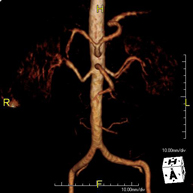

Prueba diagnóstica no invasiva que consiste en el estudio de la arteria aorta abdominal, obteniendo imágenes de alta definición anatómica mediante el empleo de un campo electromagnético y ondas de radio (con un emisor y un receptor). Es indispensable el uso de contraste paramagnético (Gadolinio). Sin embargo, no utiliza radiación ionizante. La calidad de las imágenes permite realizar reconstrucciones en 2D y 3D. Está indicado en aquellos pacientes con enfermedad vascular (aterosclerosis), estudio de aneurismas, en estudios pre-quirúrgicos de lesiones adyacentes a la aorta abdominal como "mapa" vascular, etc. - Angio RM Aorta-ilíaca

Prueba diagnóstica no invasiva que consiste en el estudio de la arteria aorta abdominal de las arterias ilíacas, obteniendo imágenes de alta definición anatómica mediante el empleo de un campo electromagnético y ondas de radio (con un emisor y un receptor). Es indispensable el uso de contraste paramagnético (Gadolinio). Sin embargo, no utiliza radiación ionizante. La calidad de las imágenes permite realizar reconstrucciones en 2D y 3D. Esta prueba está especialmente indicada como estudio pre-quirúrgico (mapa vascular) antes de intervenciones percutáneas o quirúrgicas de aorta abdominal y arterias ilíacas, estudio complementario en pacientes con isquemia de miembros inferiores, etc. - Angio RM Arterial extremidades inferiores

Prueba diagnóstica no invasiva que consiste en el estudio de la arteria aorta abdominal, obteniendo imágenes de alta definición anatómica mediante el empleo de un campo electromagnético y ondas de radio (con un emisor y un receptor). Es indispensable el uso de contraste intravenoso paramagnético (gadolinio). Sin embargo, no utiliza radiación ionizante. La calidad de las imágenes permite realizar reconstrucciones en 2D y 3D. Está indicado en aquellos pacientes con enfermedad vascular (aterosclerosis), estudio de aneurismas, en estudios pre-quirúrgicos de lesiones adyacentes a la aorta abdominal como "mapa" vascular… - Angio-RM Aorta iliaca

Prueba diagnóstica no invasiva que consiste en el estudio de la arteria aorta abdominal, obteniendo imágenes de alta definición anatómica mediante el empleo de un campo electromagnético y ondas de radio (con un emisor y un receptor). Es indispensable el uso de contraste intravenoso paramagnético (gadolinio). Sin embargo, no utiliza radiación ionizante. La calidad de las imágenes permite realizar reconstrucciones en 2D y 3D. Esta prueba está especialmente indicada como estudio pre-quirúrgico (mapa vascular) antes de intervenciones percutáneas o quirúrgicas de aorta abdominal, estudio complementario en pacientes con isquemia de miembros inferiores… - Angio-RM Arterias renales